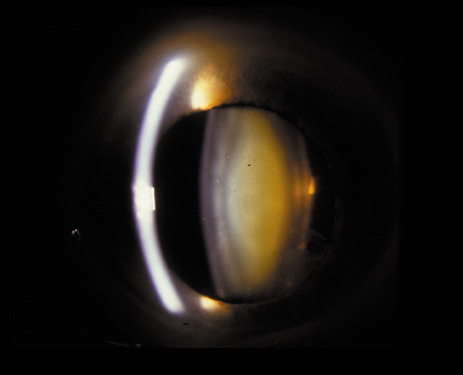

Cortical opacities have been clinically observed to develop earliest in the inferior half of the lens, especially the lower nasal quadrant.28 Epidemiologic29 and laboratory studies30 have suggested that cortical cataracts may be caused by ultraviolet rays from sunlight. The supraorbital margins may block the ultraviolet rays from falling over the upper part of the lens, thus making cortical cataract less frequent in the upper quadrants. Eventually these opacities also develop in the periphery in other quadrants, resulting in a circular array of spokes and peripheral cuneiform opacities (Fig. 9). Bands of central cortical fibers may become prominent and opacify centrally (Fig. 10). However, most cortical cataracts remain in the periphery for many years, even decades, before the central axis of the lens becomes involved, causing loss of vision late in the development of the cataract.

Fig. 9. Moderate cortical changes. Wedge-shaped (cuneiform) or spoke-like (wheel) peripheral changes are seen. These changes may be extensive but may not affect Snellen visual acuity since they occur in the periphery.

It has been observed that some individuals may have cortical opacities covering the entire anterior cortical and posterior cortical area (Fig. 11), and yet have 20/40 or better Snellen visual acuity under standard testing conditions. However, these patients may have severe disability glare such that under simulated bright lights their visual acuity may decrease to 20/80 or worse.31 They may also have decreased contrast sensitivity. These individuals tend to do well indoors but have difficulty driving during bright, sunny days, and at night because of oncoming headlights. Treatment in these cases must be decided on an individual basis, and surgery may be indicated when the expected benefits outweigh the surgical risks.

Fig. 11. Advanced cortical cataract. Although this type of cataract may be compatible with a Snellen visual acuity of 20/40 or better, it may give rise to severe glare disability.

This type of cataract is best seen with retroillumination, which gives an enhanced picture of the cortical spokes and vacuoles by the shadows they cast as the light is reflected back by the fundus. Direct illumination helps clarify the level of the opacities (see discussion in the Posterior Subcapsular Cataract section below).